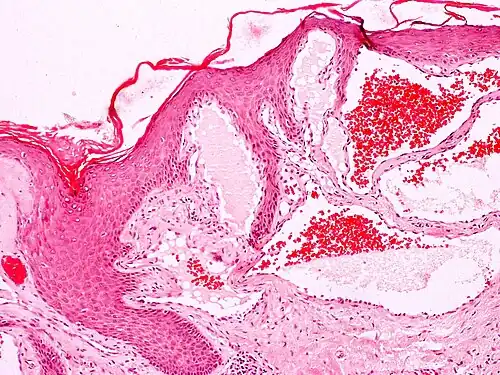

Angiokeratomas characteristically have large dilated blood vessels in the superficial dermis and hyperkeratosis (overlying the dilated vessels).

Scrotal angiokeratoma; visible large dilated blood vessels and hyperkeratosis -

Scrotal angiokeratoma (Fordyce type); dilated cavernous capillaries, acanthosis